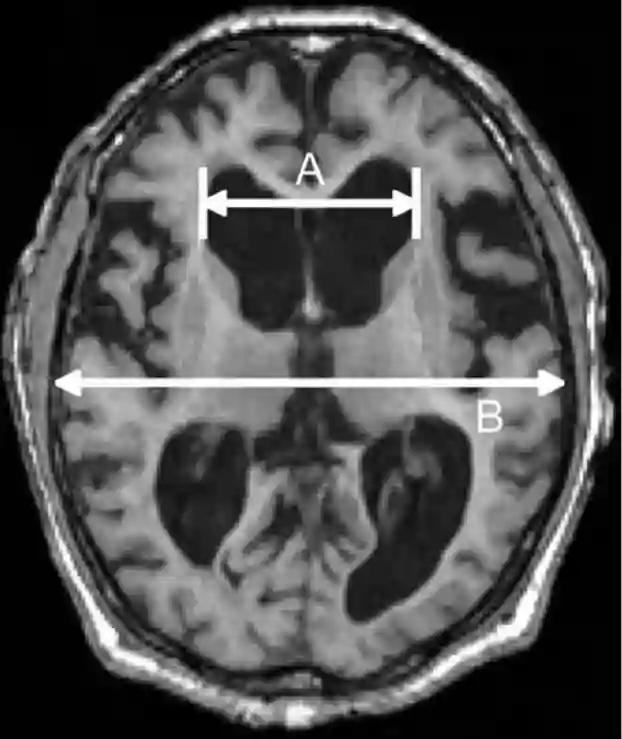

Der Evans Index ist das Verhältnis zwischen der maximalen Weite der Vorderhörner der Seitenventrikel auf einem axialen Schnittbild und dem maximalen inneren Durchmesser des Schädels auf derselben Schicht.

Evans Index MRI

Der Evans Index wird anhand dieses axialen MRI Schnittsbild mit A/B berechnet.